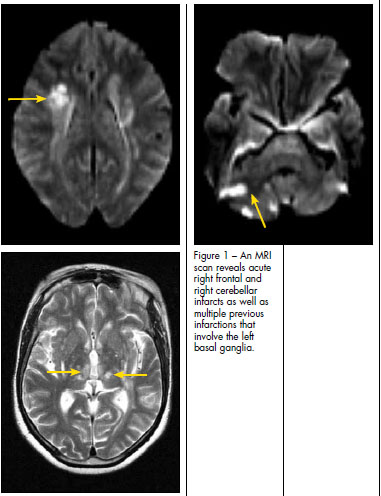

A CT scan of the head revealed several age-indeterminate lacunar infarcts and generalized atrophy. An MRI scan (Figure 1) showed acute right frontal and right cerebellar infarcts as well as multiple previous infarctions. Because of the patient's history of recurrent cerebrovascular events, additional studies were ordered. The results of carotid artery ultrasonography and transthoracic echocardiography were normal. However, transesophageal echocardiography demonstrated Lambl excrescences along coaptation points on the aortic valve (Figure 2).